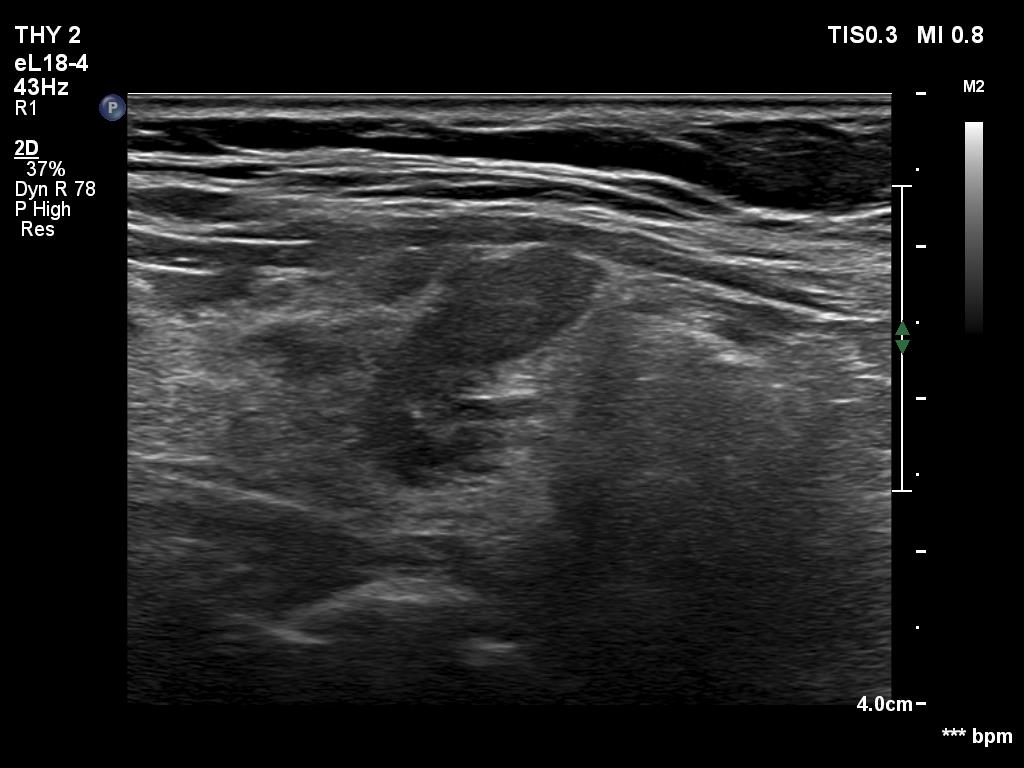

Ultrasonography. The thyroid was mainly composed of hypoechoic islets which floated in less hypoechoic background. These lesions had irregular, lobulated margins and showed no vascularity.

Comment. The presentation was not entirely characteristic of Hashimoto's thyroiditis. Nevertheless, the multiplicity of the lesions, the irregular borders and the moderately hypoechoic non-lesional part of the lobe all argued for being these lesions not true nodules but more active foci of thyroiditis.